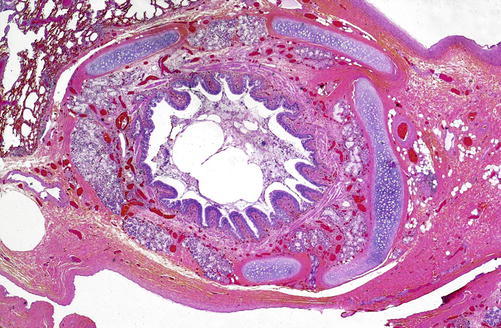

In bacterial sepsis, microscopically, seeding of the bacteria in one or multiple organs can be present. Fibrin microthrombi may be seen within the microvasculature of various organs. Increased numbers of segmented neutrophils may be present within the microvasculature, in particular the lungs and hepatic sinusoids. The bone marrow may show an increase in myeloid precursors (so-called left shift). Edema and mixed inflammation can sometimes be seen in the myocardium or there may be valvular endocarditis (Fig. 30.4a, b). Cellular injury and evidence of apoptosis may be seen in multiple organs.

Fig. 30.4.

(a) Vegetation with acute bacterial endocarditis (Hematoxylin and Eosin, H&E × 4) showing acute inflammatory cells and fibrin (b) vegetation, high-magnification Gram stain showing Gram-positive bacteria consistent with acute bacterial endocarditis (×4)